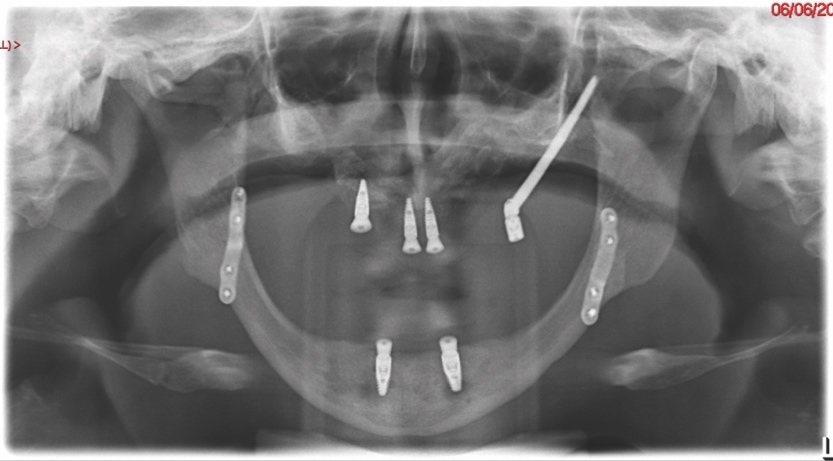

Six months after the first surgical procedure, a CBCT scan was taken in order to assess the position of the mandible to the maxilla and MDT discussions were repeated. Radiographic evaluation revealed appropriate healing with stable bone height. The patient then underwent the second stage of her surgical management, and transzygomatic implants (maxilla) and conventional dental implants (mandible) were inserted.

Bone level fixtures were placed in the intraforaminal region with submerged healing, and axially loaded. After alveolar ridge height reduction to facilitate implant placement in the apico-coronal position, one Southern zygomatic implant (Zygex with uniabutment and healing cap) was placed in the left quadrant and three 10mm bone-level implants (021.3310) were placed (UR4, UR1 and UL1 sites) (Figure 6). Two 12mm implants (021.5310)) were then placed in the mandible (LL3, LR2 regions).

A follow-up orthopantomogram revealed that all implants were healing well (Figure 7). The shortened dental arch (SDA) concept was used to restore this patient’s occlusion, and a maxillary bridge and mandibular implant-retained denture were used to restore second premolar to second premolar in each arch (Figures 8 and 9). SDA was introduced in 198114 and is a problem-oriented method that aims to minimise complex restorative treatments.14 It outlines maintaining at least four posterior occlusal units or a minimum of 20 well-distributed teeth to ensure a functional, natural and healthy dentition.15